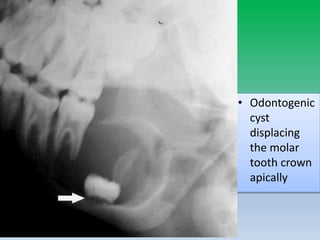

Q-Effect on surrounding structure

• Displacement of tooth

– slow-growing, space-occupying lesions

– epicentre above the crown of the tooth (i.e., dentigerous

cyst and occasionally odontomas) displace the tooth

apically.

– Lesion that start in the ramus, such as cherubism, may push

teeth in the anterior direction

• Resorption of tooth

– more chronic and slow-growing processes; however,

malignant lesions also occasionally resorb teeth.

• irregular widening and destruction of lamina dura- malignant

lesion

• Widening of mandibular canal – neurogenic or vascular lesion

• Odontogenic

cyst

displacing

the molar

tooth crown

apically